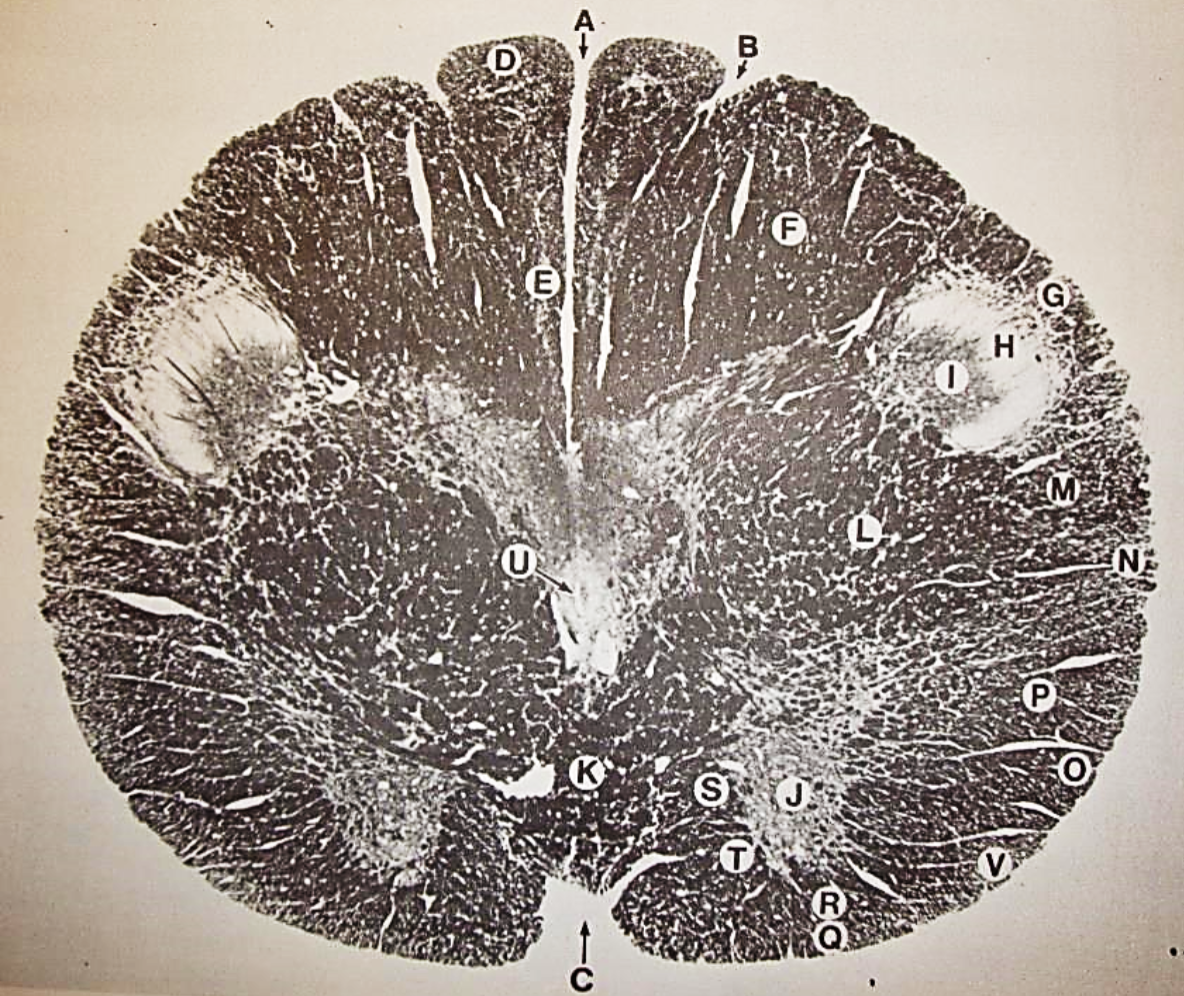

A

posterior median sulcus

B

posterior intermediate sulcus

C

anterior median fissure

D

gracile fasciculus

E

Gracile nucleus

F

fasciculus cuneatus

G

spinal trigeminal tract

H+I collectively

spinal trigeminal nucleus

J

Accessory nucleus

K

pyramidal decussation

L

lateral corticospinal tract

M

rubrospinal tract

N

posterior spinocerebellar tract

O

anterior spinocerebellar tract

P

lateral spinothalamic tract

Q

anterior spinothalamic tract

R

lateral vestibulospinal tract

S

medial longitudinal fasciculus

T

tectospinal tract

U

central canal